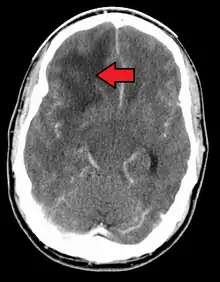

| Coronal MRI with contrast of a glioblastoma in a 15-year-old male | |

When viewed with MRI, glioblastomas often appear as ring-enhancing lesions. The appearance is not specific, however, as other lesions such as abscess, metastasis, tumefactive multiple sclerosis, and other entities may have a similar appearance.[51] Definitive diagnosis of a suspected GBM on CT or MRI requires a stereotactic biopsy or a craniotomy with tumor resection and pathologic confirmation. Because the tumor grade is based upon the most malignant portion of the tumor, biopsy or subtotal tumor resection can result in undergrading of the lesion. Imaging of tumor blood flow using perfusion MRI and measuring tumor metabolite concentration with MR spectroscopy may add diagnostic value to standard MRI in select cases by showing increased relative cerebral blood volume and increased choline peak, respectively, but pathology remains the gold standard for diagnosis and molecular characterization.